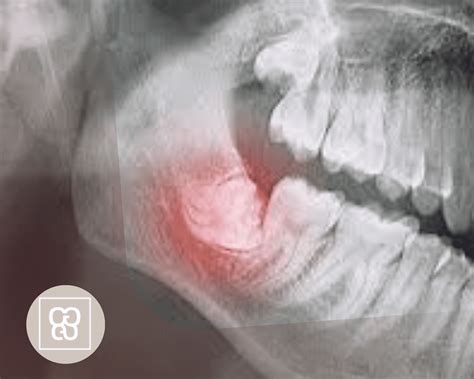

Pese a lo que muchos creen las cordales no siempre deben ser extraídas. Esto puede evaluarse mediante una radiografía, en la que se observa cómo está creciendo la pieza dental y si tiene espacio para hacerlo.

La facilidad o dificultad con la que tu dentista o cirujano maxilofacial puede extraer las muelas de juicio depende de su posición y desarrollo. El especialista tendrá una idea de qué esperar a partir de los exámenes preoperatorios.

Un tercer molar que salió completo, normalmente se puede extraer con la misma facilidad que cualquier otro diente. Pero si está debajo de las encías, más incrustado en el maxilar, si puede requerir una incisión, eliminar una porción de hueso, por lo que requerirá un proceso de extracción más complicado.